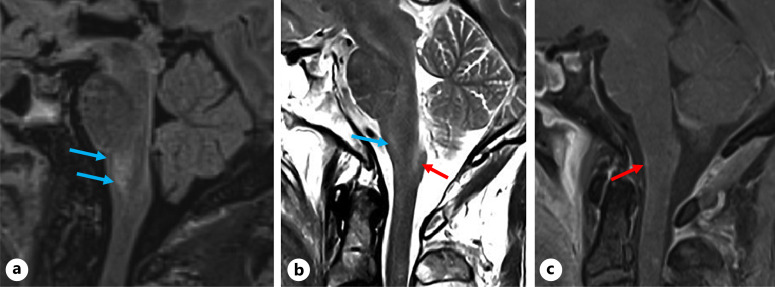

Case presentation: A previously healthy man in his 70s presented with headache, fever, and confusion, followed by a seizure and persistent hiccoughs. MRI revealed brainstem involvement and extensive transverse myelitis. Cerebrospinal fluid (CSF) analysis showed inflammatory features, but testing for AQP4, MOG, and GFAP antibodies was initially negative. He was treated with intravenous corticosteroids and plasma exchange, after which serum GFAP-IgG was weakly positive, though CSF remained negative. His condition improved with immunotherapy, but significant lower limb weakness persisted. Based on clinical and radiological findings, we hypothesize that tanycytes - specialized glial cells in the area postrema - may be an additional immune target in GFAP encephalitis.